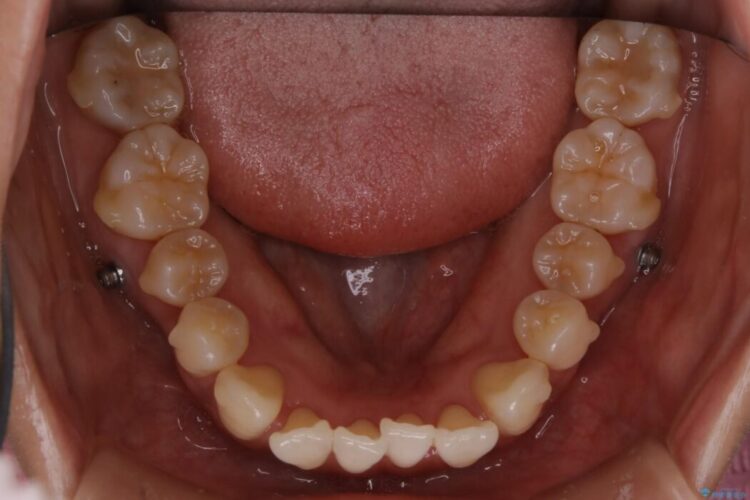

前歯のガタガタを気にされて来院されました。

検査の結果、骨の厚みに余裕がないことが判明しましたので、幅の拡大と歯の側面を削るIPRでは歯周病に対する不安を拭いきれないと判断しました。

よってマイクロインプラントを用い、奥歯から順番に遠心移動させることによってスペースを確保することにしました。